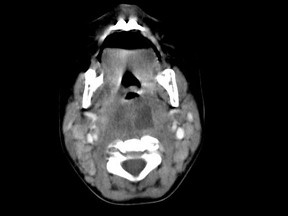

[多选题] 10个月大的婴儿,发热,曾患中耳炎,CT扫描如图所示,正确的描述或诊断是()A . 咽后壁软组织肿胀B . 其内密度不均C . 颈椎骨质未见明显异常D . 咽后壁脓肿E . 咽后壁寒性脓肿

[多选题] 10个月大的婴儿,发热,曾患中耳炎,CT扫描如图所示,正确的描述或诊断是()A .咽后壁软组织肿胀B .其内密度不均C .颈椎骨质未见明显异常D .咽后壁脓肿E .咽后壁寒性脓肿

[多选题] 10个月大的婴儿,发热,曾患中耳炎,CT扫描如图所示,请选择正确的描述或诊断()A . 咽后壁软组织肿胀B . 其内密度不均C . 颈椎骨质未见明显异常D . 考虑为咽后壁脓肿E . 考虑为咽后壁寒性脓肿

[多选题] 10个月大的婴儿,发热,曾患中耳炎,CT扫描如图所示,请选择正确的描述或诊断()A .咽后壁软组织肿胀B .其内密度不均C .颈椎骨质未见明显异常D .考虑为咽后壁脓肿E .考虑为咽后壁寒性脓肿